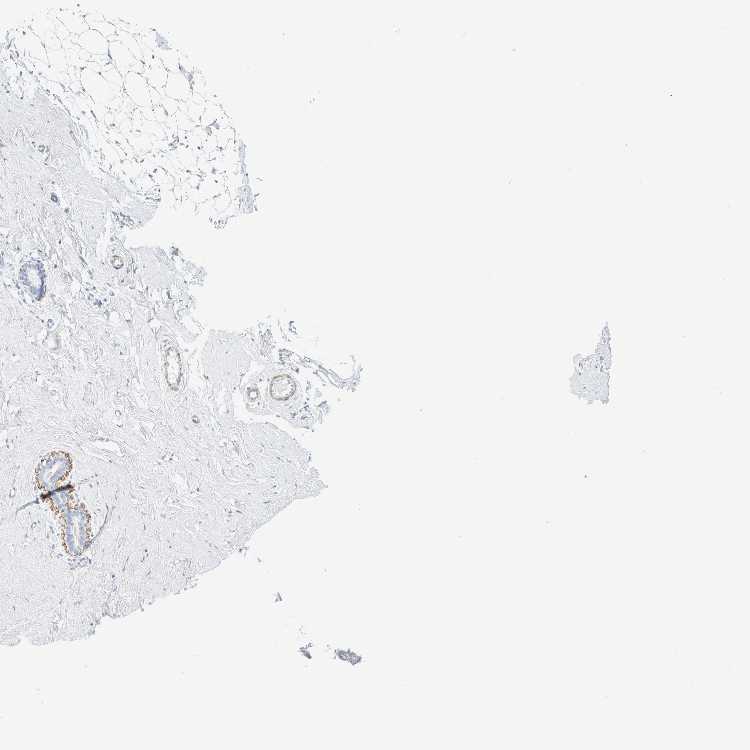

BREAST - Antibody stainingi

Antibody staining in the annotated cell types in the current human tissue is reported as not detected, low, medium, or high, based on conventional immunohistochemistry profiling in selected tissues. This score is based on the combination of the staining intensity and fraction of stained cells.

Each image is clickable and will lead to virtual microscopy that enables deeper exploration of all samples and also displays staining intensity scores, fraction scores and subcellular localization as well as patient and tissue information for each sample.

Antibody HPA023861Antibody HPA026536

Adipocytes Not detectedNot detected

Glandular cells Not detectedNot detected

Myoepithelial cells HighNot detected